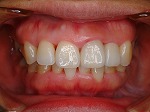

歯をより白く綺麗にしたいと思う方々は多いと思います。審美歯科とは、白い歯が見える口元だけではなく、機能的で歯周組織と顔貌に調和した自然美を追求する治療です。治療は短期間(歯冠修復・ホワイトニングなど)で終わるものから長期に渡る全顎的な治療(歯周病治療・矯正治療・インプラント治療など伴うケース)を行う症例もあります。当院での歯冠修復は

- ジルコニアクラウン修復

- メタルボンドクラウン修復

- グラスセラミッククラウン修復

- ハイブリットインレー、アンレー修復

- コンポジットレジン充填

等の歯冠修復を行っています。

◆ジルコニアクラウン修復

→